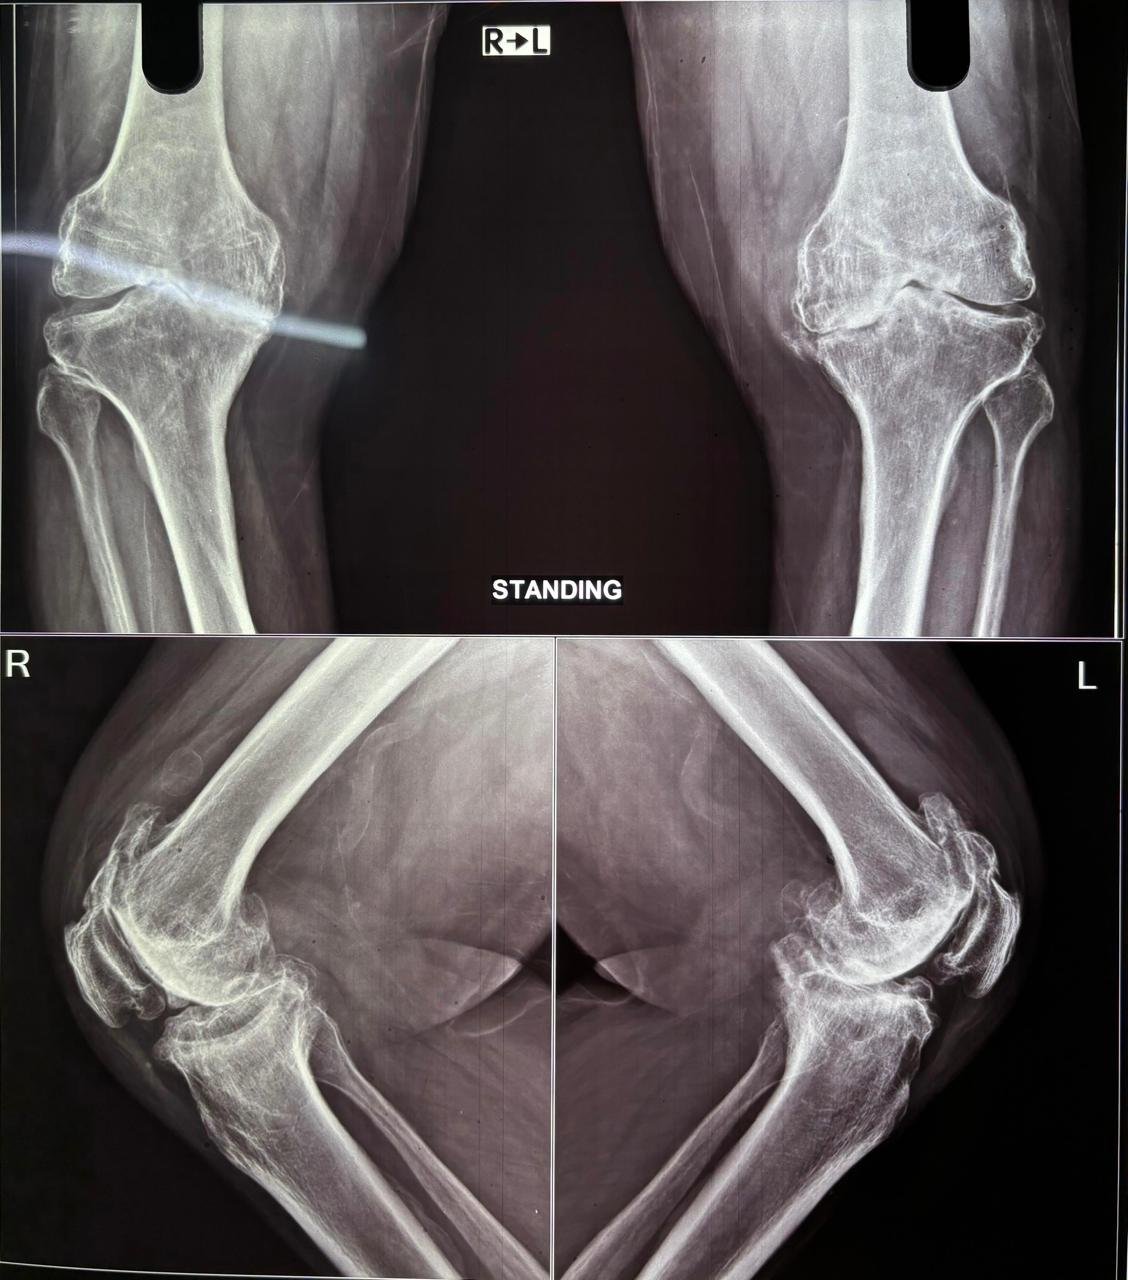

Pre-Op X-Ray